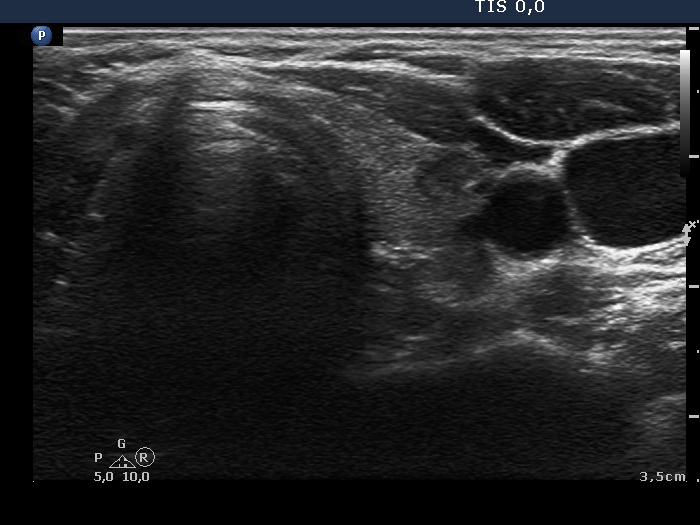

Follow-up 3 years later (ultrasonographic picture 6)

Lower part of the left lobe, transverse scan. Discrete hypoechogenic lesions are frequent findings in Hashimoto's thyroiditis. We do not think that this small mass might correspond to an enlarged parathyroid.